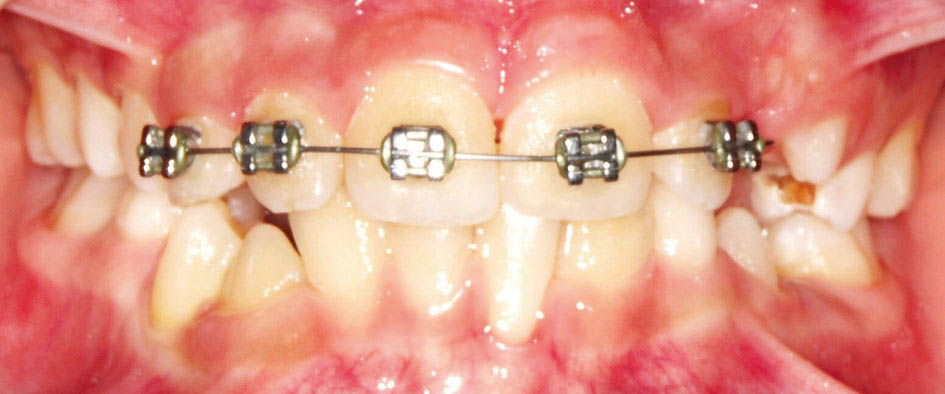

وقتی یک دندان در کراس باشد (شکل 26-5) میتوانید برای فک پائین یک اسپلینت آکریلی بسازید و چند براکت روی دندانهای بالا بچسبانید و به کمک یک سیم 0.012 سوپرالاستیک قدامیهای بالا را پروترود کنید تا از کراس خارج شوند (شکل 27-5 الی 28-5).

شکل 28-5: قراردادن سیم نازک سوپرالاستیک 0.012 برای پروترود شدن انسیزورها و اسپلینت آکریلی متحرک پائین جهت باز کردن بایت